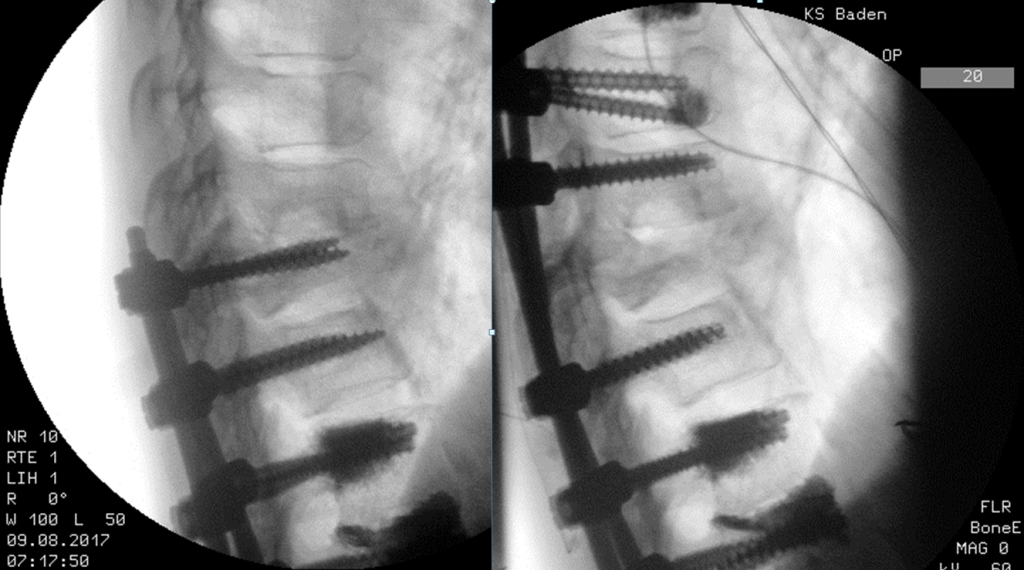

Wenn wir älter werden, nehmen die Verschleisserkrankungen zu. Und die Wirbelsäule verliert oft die gerade, aufrechte Struktur und wird krumm und krümmer. Im Röntgenbild sehen wir oft ganz verschiedene Verschleisssituationen nebeneinander. Da die Wirbelsäule aus verschiedenen Bewegungssegmenten besteht, muss der Wirbelsäulenchirurg genau wissen, woher der Schmerz kommt. Würde man sich…